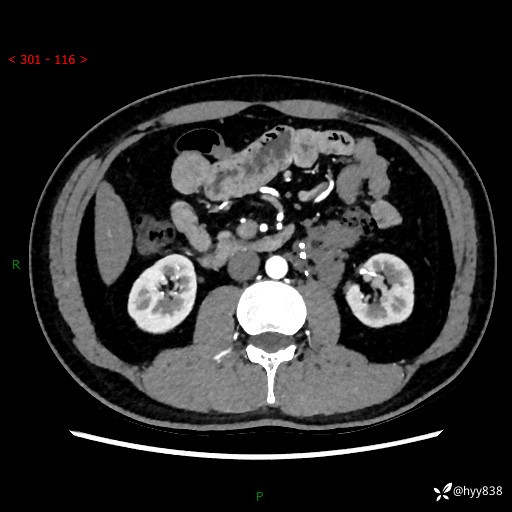

现病史:患者3月余前检查发现左侧腹膜后占位,大小约3.7*4.9cm,平素无腰疼,无肉眼血尿,无尿频尿急等不适,当时未特殊处理,在门诊复查CT提示左侧腹膜后占位,门诊拟“左侧腹膜后占位”收入院。 起病以来,患者精神佳,饮食、睡眠良好,大小便正常,体力体重无明显变化。

腹膜后CT平扫+增强